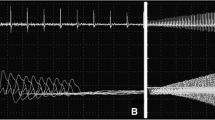

The functional effects of specific RYR1 mutations have been studied in response to IVCT, in cultured myotubes from patients and in various homologous and heterologous expression systems. Early studies already suggested an association between specific RYR1 mutations and IVCT response [75], and indicated a correlation between the particular RYR1 gene mutation in a family and the severity of MH or liability to CCD [26, 76]. In vitro studies on human myotubes demonstrated both increased [77, 78] and reduced [79, 80] agonist sensitivity depending on the precise location of the RYR1 mutation investigated. Studies on a RYR1 C-terminus mutation (I4898T) associated with a severe CCD phenotype demonstrated reduced intracellular calcium release without increasing the sensitivity to caffeine or halothane [36] and a marked disturbance of excitation-contraction coupling [81]; the latter may also apply for other C-terminal mutations [82]. Studies of RYR1 mutants expressed in myotubes of RYR1 knockout ("dyspedic") mice [83, 84] indicate that mixed MHS/CCD mutations are associated with increased channel activity sufficient to deplete sarcoplasmic reticulum calcium stores, elevated intracellular calcium levels and reduced maximum voltage gated calcium release [79], whereas MH-only mutations appear to increase basal release channel activity insufficiently to alter net sarcoplasmic reticulum calcium content ("compensated leak"). Expression of a functional RyR1 protein in B-lymphocytes has been recently described and offers a novel approach to study the pathogenesis of RYR1 mutations in vitro. B-lymphocytes harbouring CCD-related RYR1 mutations show depletion of sarcoplasmic reticulum stores secondary to unprompted calcium release [59, 85]; increased release of inflammatory cytokines in the same study population [86] may also point at a role of RYR1 in immunomodulation.